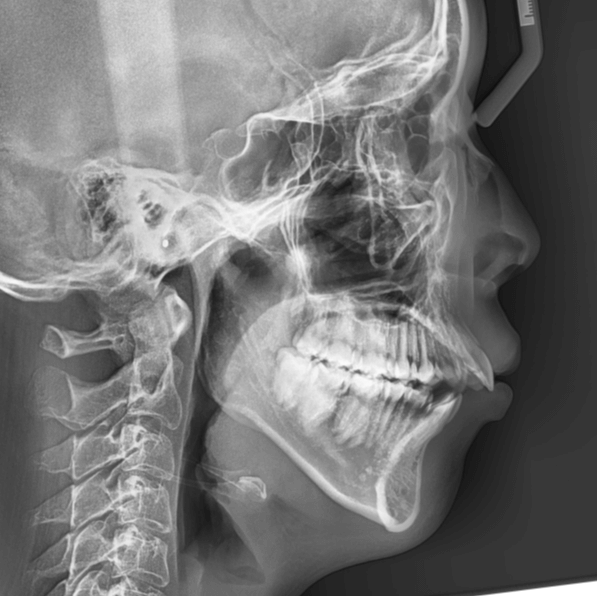

| 年齢・性別 | 25歳の女性 |

|---|---|

| 主訴 | 口元の突出感を気にされて来院された。咬み合わせや審美的な改善を希望されていました。 |

| 治療期間・回数 | 3年6ヶ月・30回 |

| 費用 | 1,000,000円 |